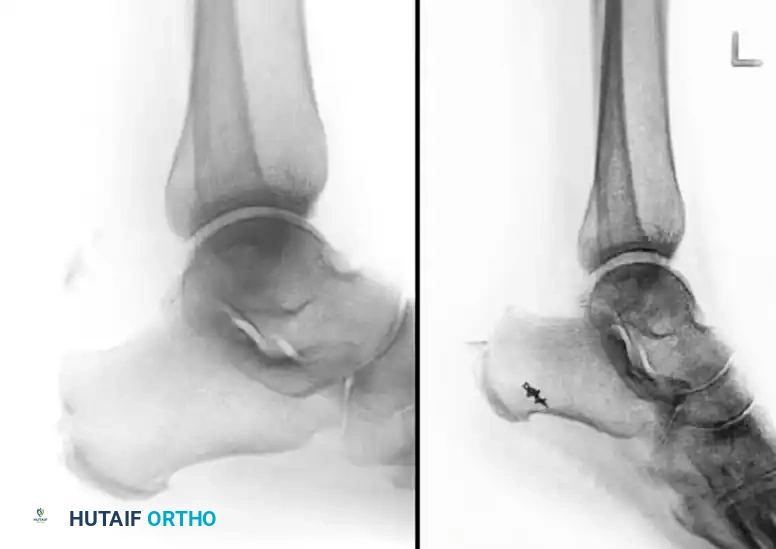

1. Plate and Screw Fixation

For large, robust Type II beak fractures, lag screw fixation supplemented by a neutralization plate provides excellent biomechanical stability. The plate acts to buttress the fragment against the massive pull of the triceps surae.

Anteroposterior and lateral radiographs demonstrating rigid plate and screw fixation of a type II calcaneal avulsion fracture.

Radiograph demonstrating precise internal fixation of an isolated sustentaculum fracture with a single lag screw.